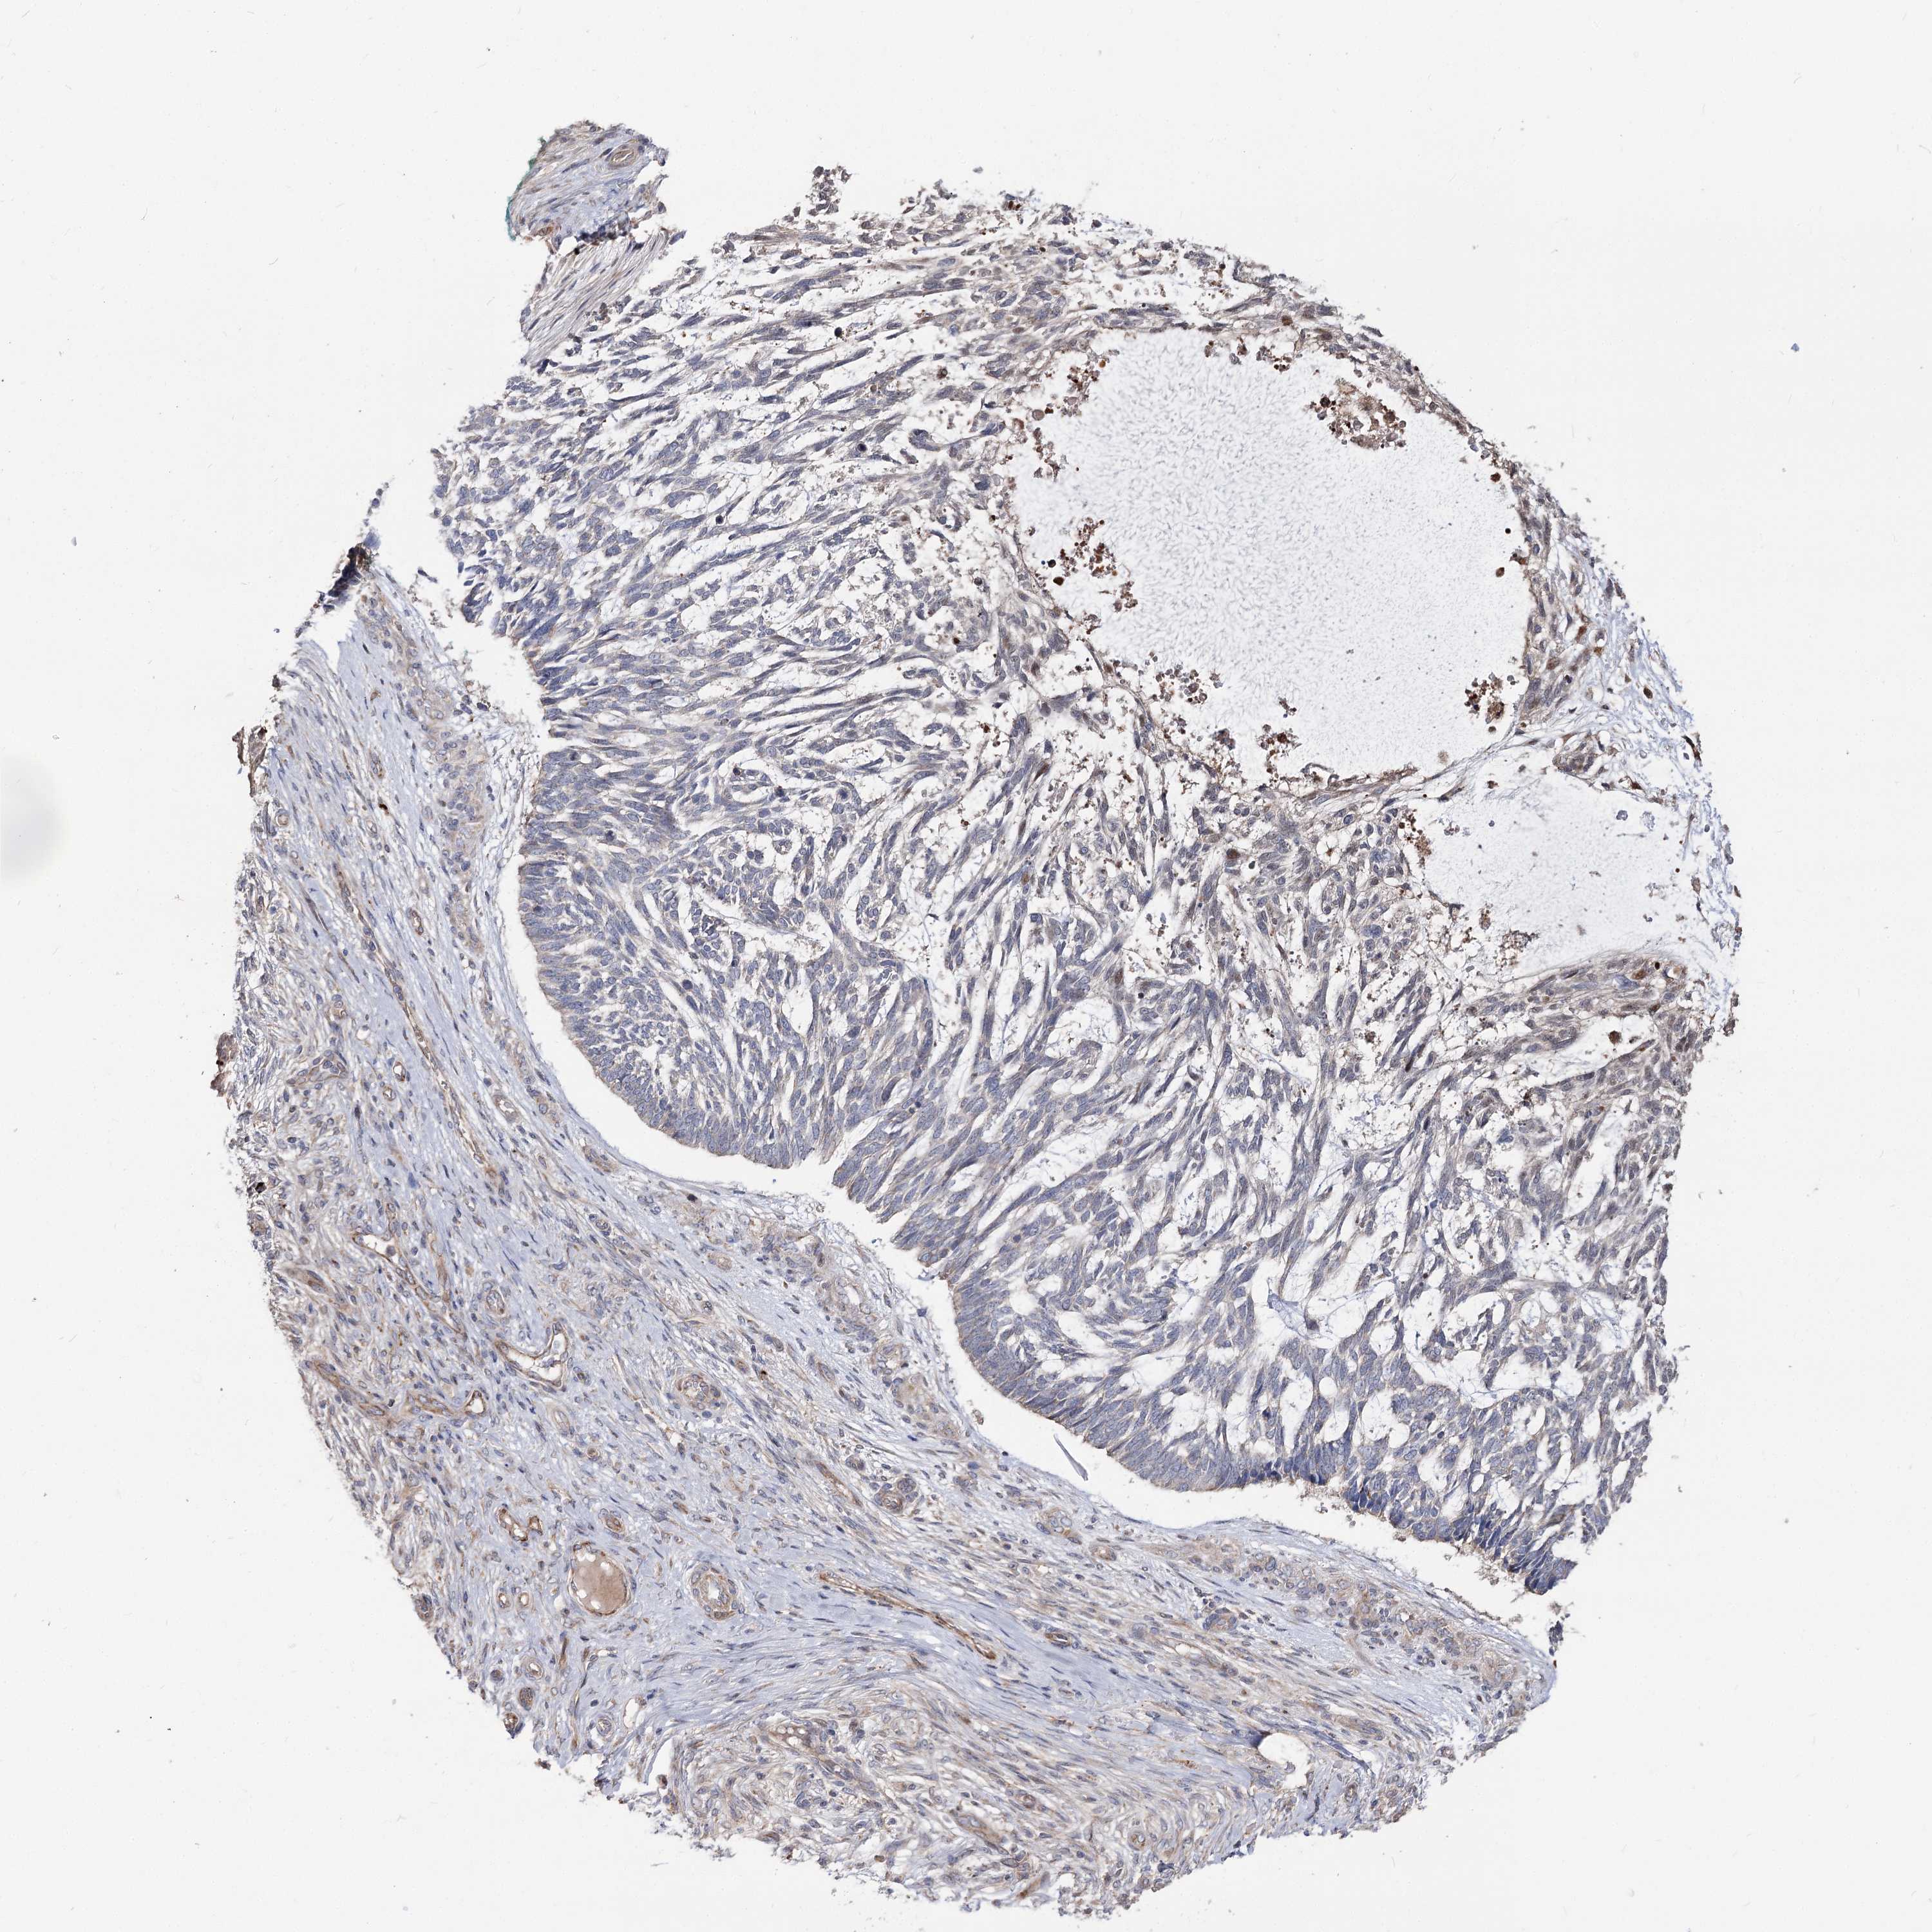

Basal cell and squamous cell cancer

SKIN CANCER - Protein expressioni

A mouse-over function shows sample information and annotation data. Click on an image to view it in a full screen mode. Samples can be filtered based on level of antibody staining by selecting one or several of the following categories: high, medium, low and not detected. The assay and annotation is described here.

Antibody stainingi

Antibody staining in the annotated cell types in the current human tissue is reported as not detected, low, medium, or high, based on conventional immunohistochemistry profiling in selected tissues. This score is based on the combination of the staining intensity and fraction of stained cells.

Each image is clickable and will lead to virtual microscopy that enables deeper exploration of all samples and also displays staining intensity scores, fraction scores and subcellular localization as well as patient and tissue information for each sample.

Antibody HPA038040

Squamous cell carcinoma, NOS

Squamous cell carcinoma, metastatic, NOS